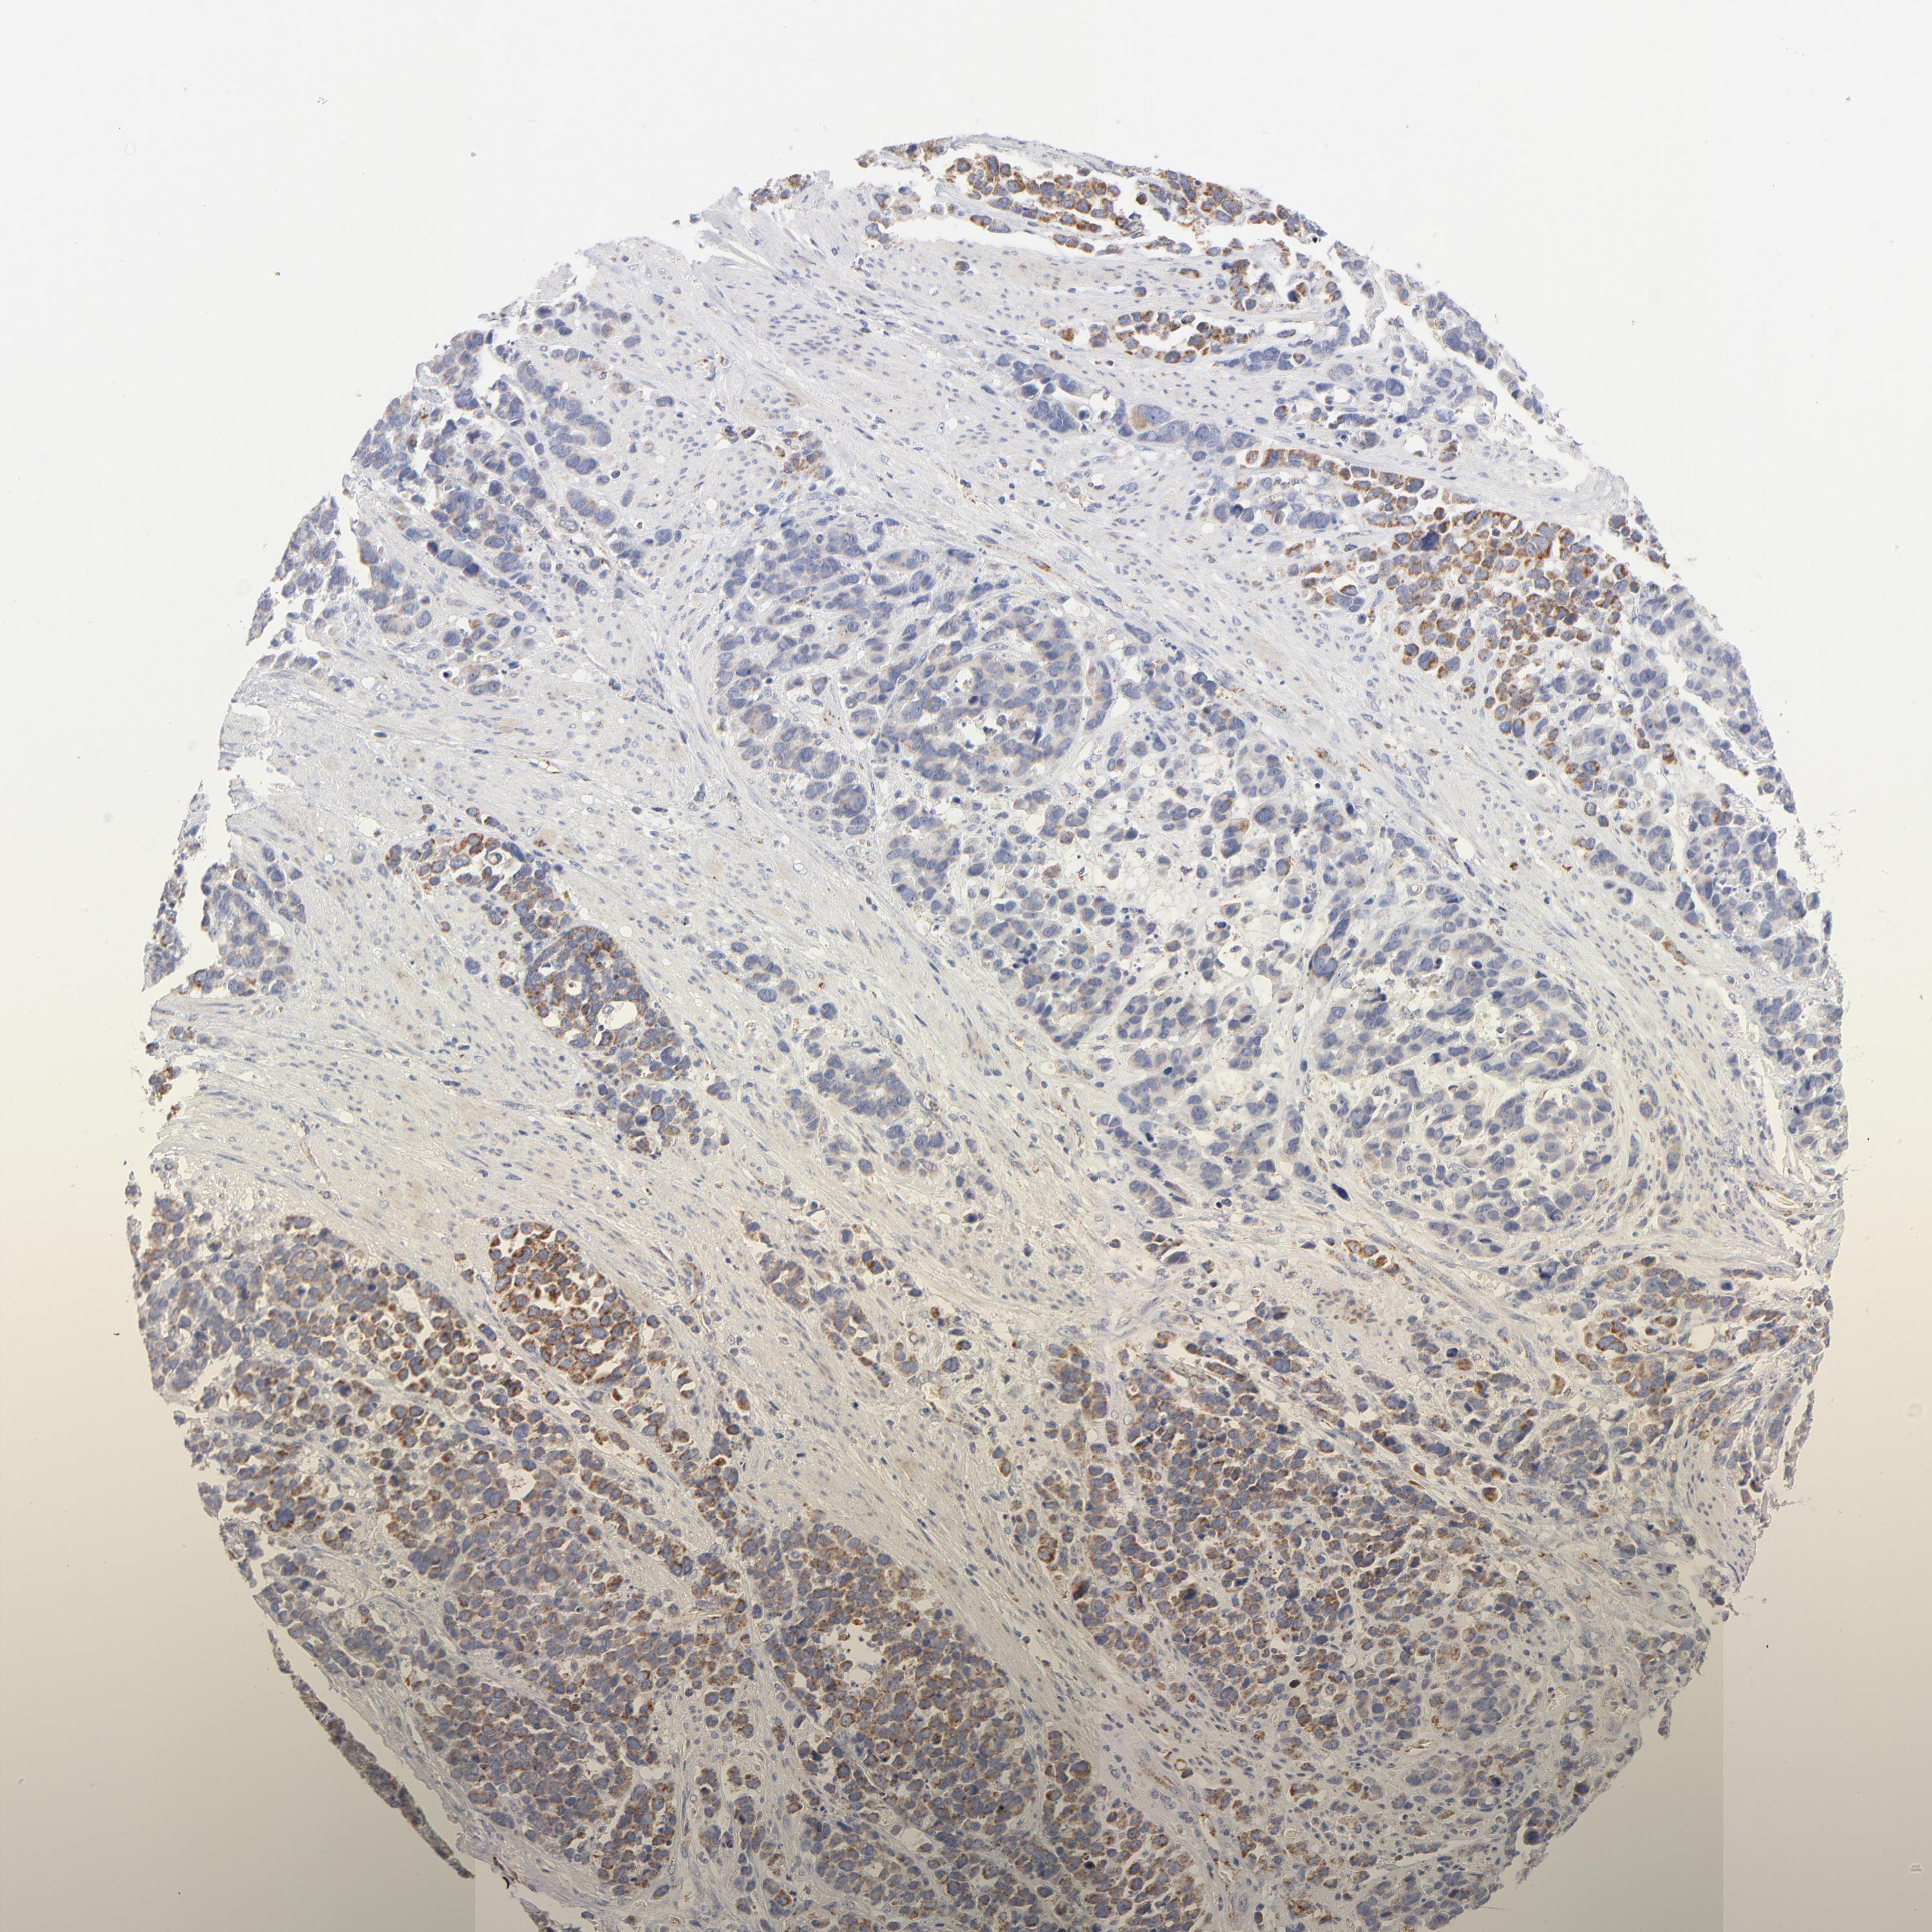

STOMACH CANCER - Protein expressioni

A mouse-over function shows sample information and annotation data. Click on an image to view it in a full screen mode. Samples can be filtered based on level of antibody staining by selecting one or several of the following categories: high, medium, low and not detected. The assay and annotation is described here.

Antibody stainingi

Antibody staining in the annotated cell types in the current human tissue is reported as not detected, low, medium, or high, based on conventional immunohistochemistry profiling in selected tissues. This score is based on the combination of the staining intensity and fraction of stained cells.

Each image is clickable and will lead to virtual microscopy that enables deeper exploration of all samples and also displays staining intensity scores, fraction scores and subcellular localization as well as patient and tissue information for each sample.

Antibody HPA040786

Antibody CAB003782

Staining

High

Medium

Low

Not detected

Intensity

Strong

Moderate

Weak

Negative

Quantity

>75%

75%-25%

<25%

None

Location

Nuclear

Cytoplasmic/membranous

Cytoplasmic/membranous,nuclear

Adenocarcinoma, NOS